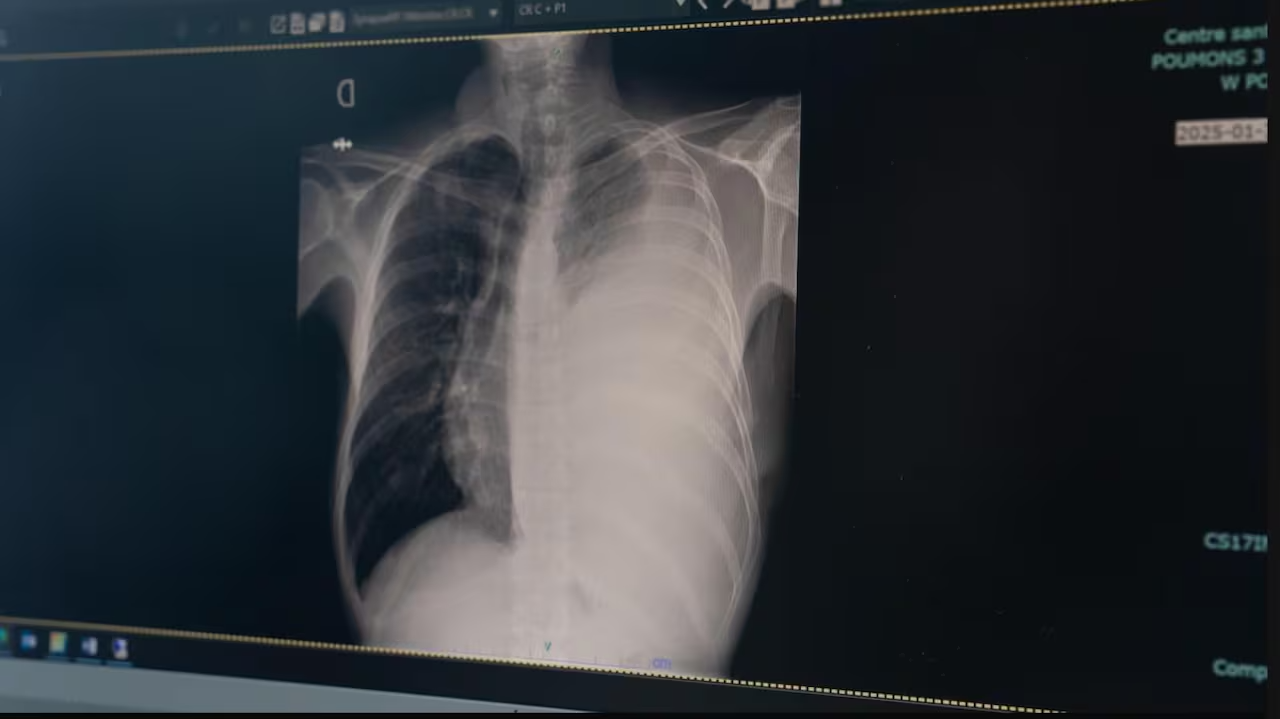

Nunavik health board’s infectious disease clinical lead, Yassen Tcholakov, said tuberculosis, while curable, kills most infected patients within a few years if left untreated. Those who are treated are sometimes left with lifelong problems like scarring on their lungs. Félix Lebel/Radio-Canada

Tuberculosis is an infectious disease that usually affects the lungs, but can affect other parts of the body. It can spread when an infected person coughs, sneezes and spits, but is treatable with antibiotics.